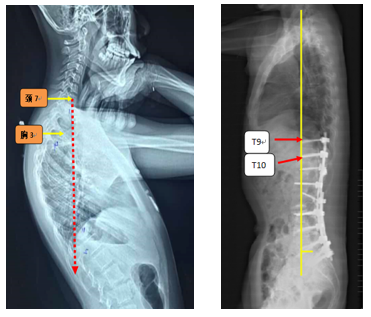

T10骨盆固定,出现交界性后凸

行翻修手术:T9/10SP截骨,延长到T4固定,预防性双侧肋骨固定(VEPTR)

图32-33 肋骨固定